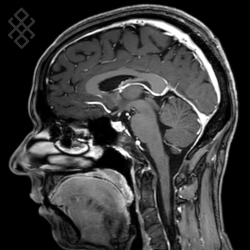

IRM Cérébrale

Vous entrez dans l'aimant, ouvert des 2 côtés, la tête la première et allongé sur le dos. Ensuite, pour recueillir le signal et construire les images, vous aurez la tête dans une antenne. Cet examen est très bruyant. Pour atténuer le bruit de la machine, vous aurez à votre disposition des tampons auriculaires.

La durée moyenne de l'examen est de 25 min. Dans le cas d'une injection, le manipulateur en radiologie vous administrera le produit de contraste. Vous entendrez un bruit caractéristique à l'IRM faisant penser à un marteau piqueur.